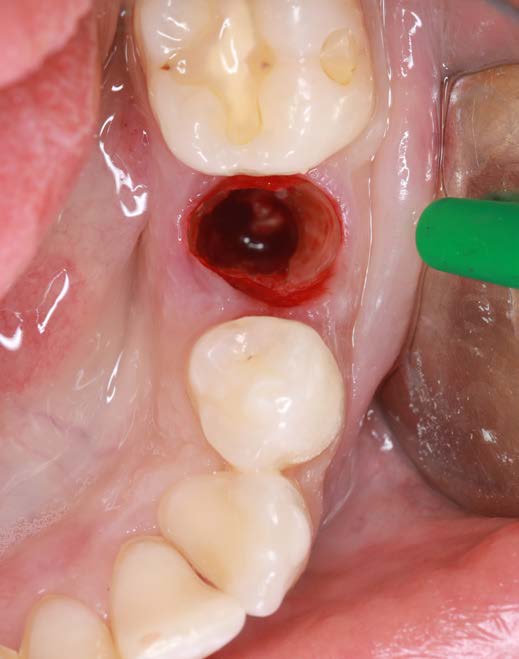

Figure 3: Condition after extraction and preservation of the buccal root portion |

A 26-year-old female patient was referred to my practice. Tooth 35 was deemed non-restorable. A CBCT scan showed the buccal bone plate was missing. Especially in aesthetic zones, we aim to reduce tissue collapse post-extraction (up to 50%). We considered various ridge preservation techniques to minimize this risk.

I chose the Socket Shield Technique, a minimally invasive method to reduce tissue shrinkage and achieve better long-term aesthetic outcomes. The technique requires healthy periodontal tissue and an intact root, both of which were present. The tooth is partially extracted, leaving the buccal root portion to support the soft tissue. This maintains the buccal periodontal attachment, allowing the tissue to behave as if the tooth were still in place. Hürzeler et al. introduced this technique in 2010 to reduce tissue shrinkage during immediate implantation.